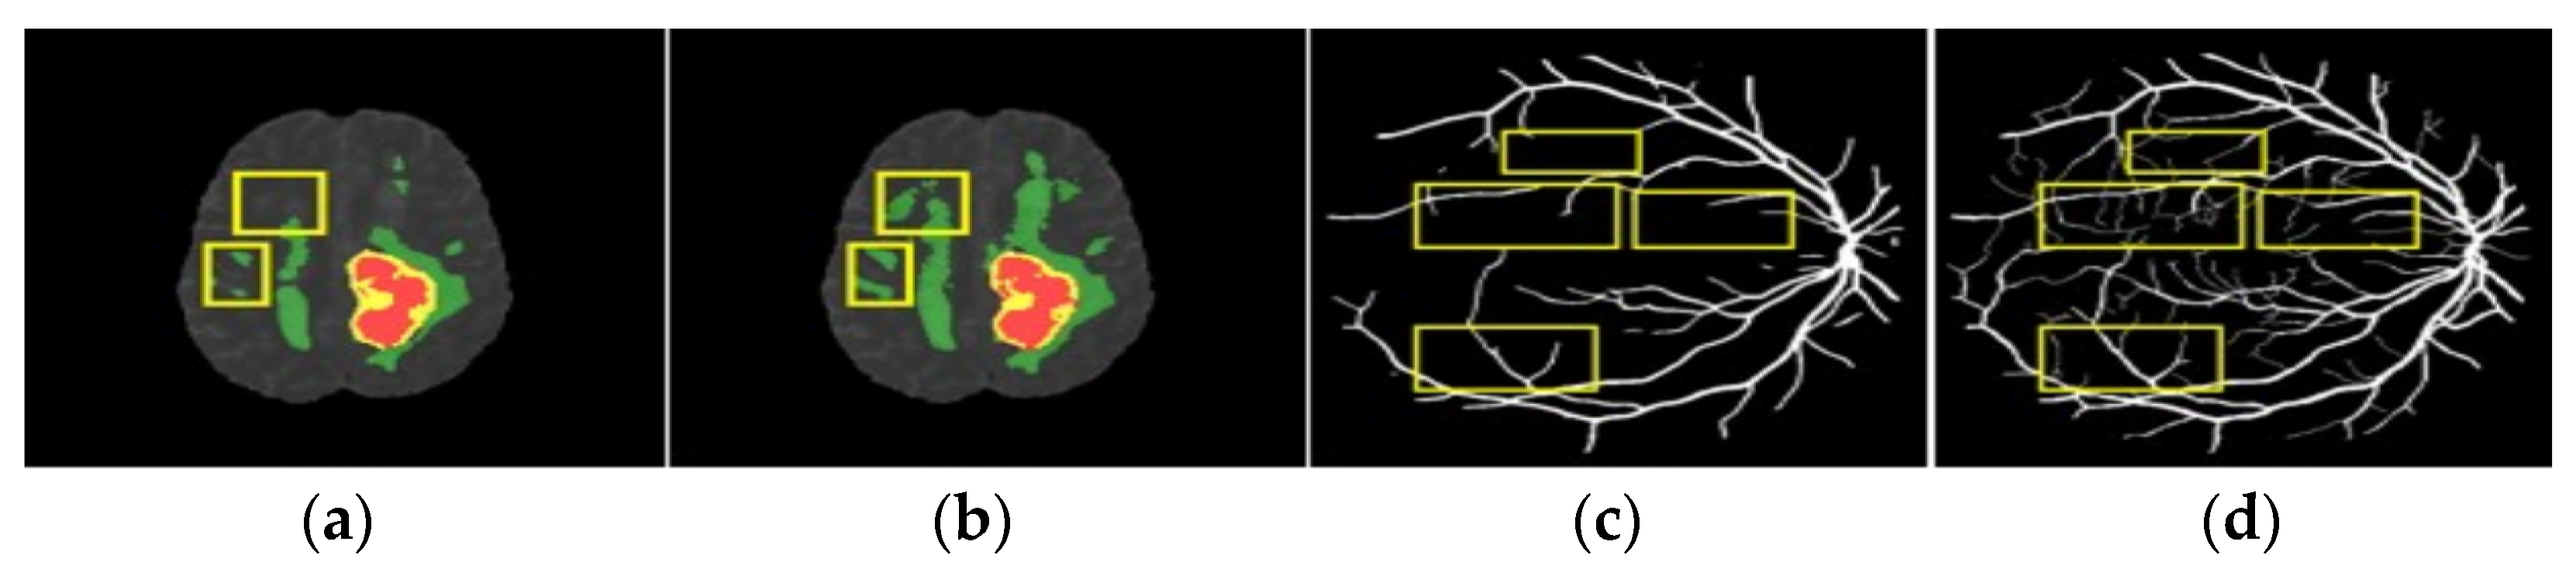

4.2. Experiment 1: BraTS Brain Tumor Segmentation

4.3. Experiment 2: DRIVE Retinal Segmentation